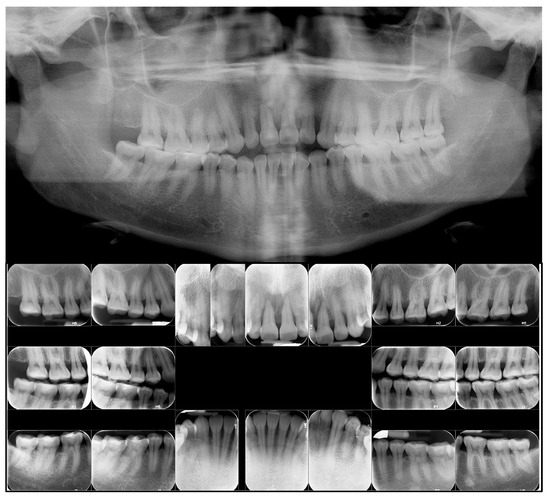

3. Treatment Results

4. Discussion